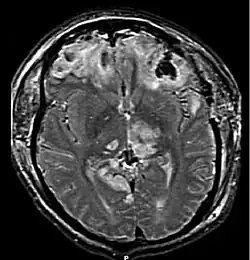

| MRI showing injury due to brain herniation | |